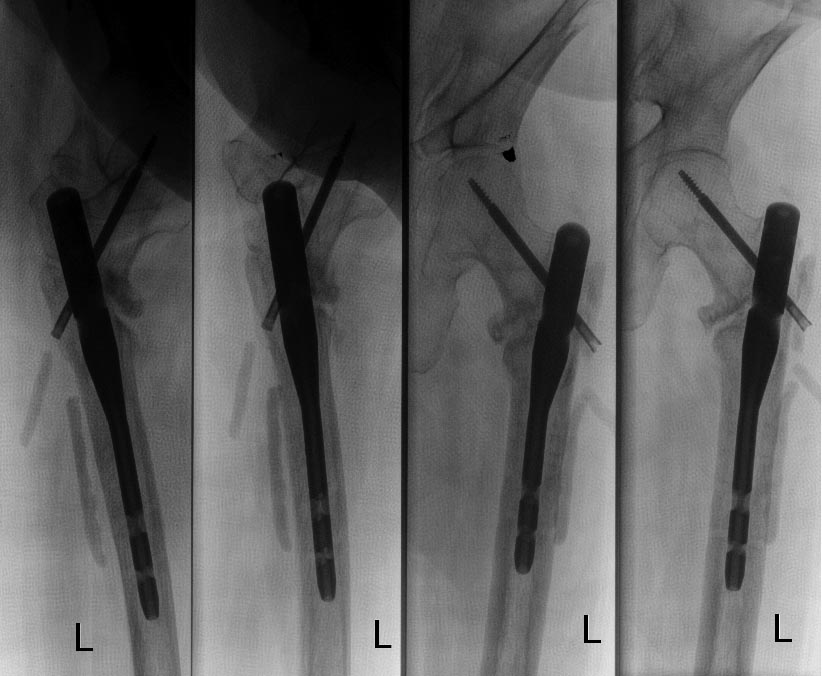

Чрезвертельный перелом левого бедра, в результате ДТП. Женщина 56 лет, ДТП. Чрезвертельный перелом. Было выполнено: скелетное вытяжение- 1 месяц, остеосинтез Г- образной пластиной (Россия), через 4 месяца второй остеосинтез, через 4 месяца вылез винт, выполнена операция- удален один винт, аллопластика. Наложена кокситная повязка. Через 2,5 месяца: щель перелома прослеживается на всем протяжении, склероз по краям отломков. Болей нет. Посоветуйте, что делать дальше, к кому и куда обратиться за помощью. Проживаю в СПб.

У нас в отделении сейчас делается довольно много операций по такого рода поводам. Предпочли бы сделать остеосинтез стержнем. Есть модификации, исключающие миграцию, подобную случившейся. Делать какие-то пластики и вообще широко обнажать кость не видно необходимости. Возможно, будет целесообразно увеличить шеечно-диафизарный угол.

Технических вариантов несколько, для выбора конкретного варианта надо посмотреть и очно, и предшествующие снимки, и сделать снимок таза с обоими тазобедренными суставами.